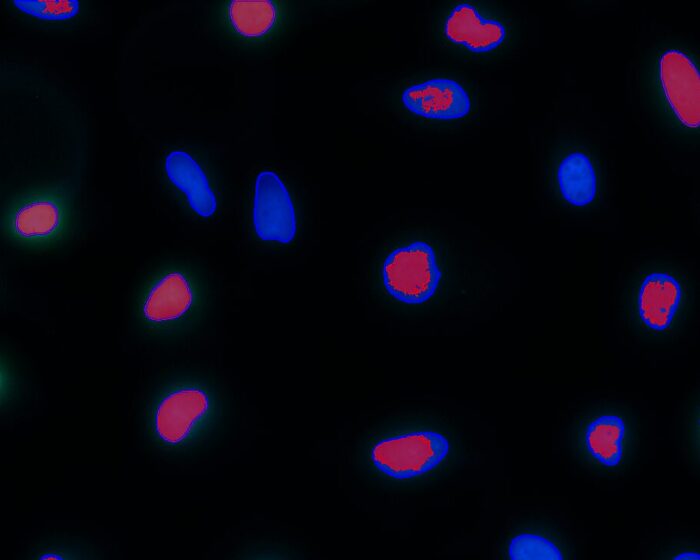

- Cancer Research

- Cell Biology

- Histology/Pathology

- Life Science